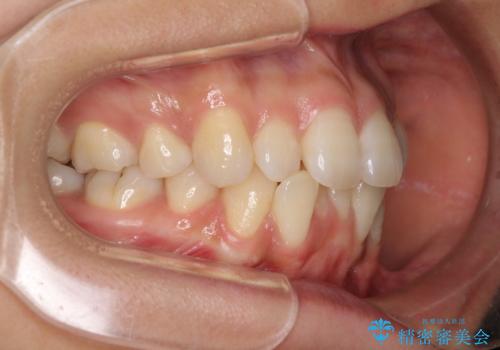

- 以前の矯正治療の後戻りにより、上下の前歯がでこぼこになってしまったことを気にして来院された患者様です。

口元がこれ以上突出することなく前歯の叢生が改善できるよう、歯と歯の間を削ってスペースを獲得し、インビザラインを用いて整えていくこととしました。

目安の装着時間である1日22時間をしっかりと実践してくださり、半年強という短期間で治療を終えることができました。